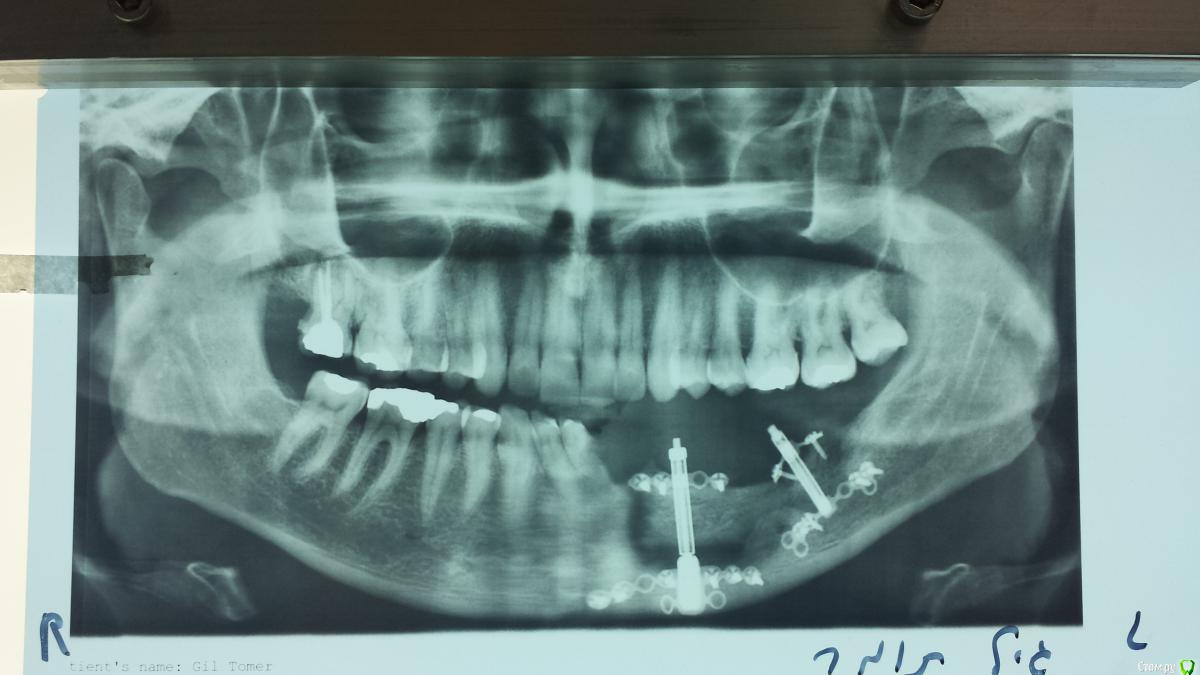

natan. Опубликовано 21 мая, 2015 Поделиться Опубликовано 21 мая, 2015 пациент после удаления амелобластомы. Был выполнен DO 4 Ссылка на комментарий

Maxfac Опубликовано 21 мая, 2015 Поделиться Опубликовано 21 мая, 2015 Два аппарата, соответственно - две зоны дистракции. Между ними была остеотомия? Оба аппарата активированы единовременно? Нет ли снимков после снятия аппаратов? Ссылка на комментарий

natan. Опубликовано 22 мая, 2015 Автор Поделиться Опубликовано 22 мая, 2015 Здравствуйте Ilgamsa, как вас по имени называть? Из за того что span (промежуток) кости огромный 31 - 37 было решено выбрать 2 дистрактора так как 2 отдельных и поменьше легче контролировать чем один длинный где ты теряешь '' силу '' по краям. Обратите внимание на '' манипуляцию''выполненную чтобы не повредить mental nerve (видно на рентген снимке с дистрактором). Активация двух сегментов кости была одновременной.в конце между двумя сегментами была добавлен bioss. Поищу снимки 2 Ссылка на комментарий